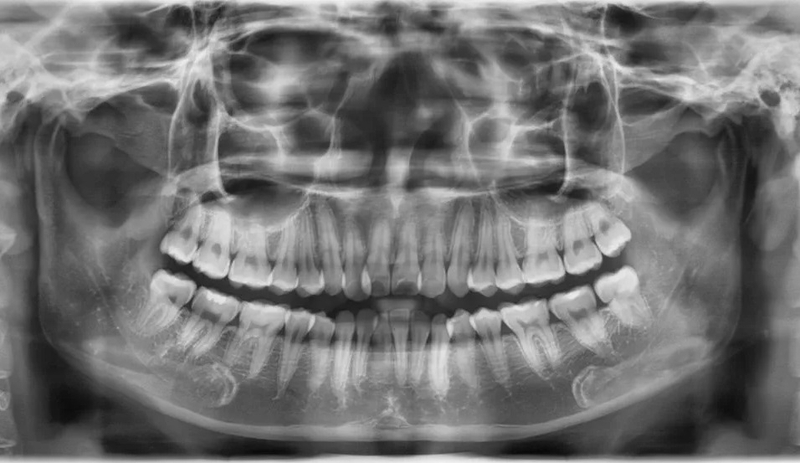

Xương hàm mỏng là tình trạng thể tích xương ổ răng quanh chân răng và thể tích xương vỏ mỏng hơn bình thường. Tình trạng xương hàm mỏng có thể xảy ra với cả xương hàm trên và xương hàm dưới. Để có thể đánh giá chính xác tình trạng xương hàm mỏng, bạn cần đến cơ sở nha khoa để chụp X-quang răng toàn cảnh. Qua hình ảnh X-quang, bác sĩ sẽ cho bạn biết xương hàm của bạn có mỏng hay không?

Xương hàm mỏng có niềng răng được không phụ thuộc vào tình trạng răng thực tế của bạn. Để có câu trả lời chính xác nhất, bạn nên tìm đến cơ sở nha khoa uy tín. Qua quá trình thăm khám và căn cứ vào kết quả chụp X-quang hàm, bác sĩ sẽ có thể tư vấn cho bạn phương án chỉnh nha an toàn và hiệu quả nhất.